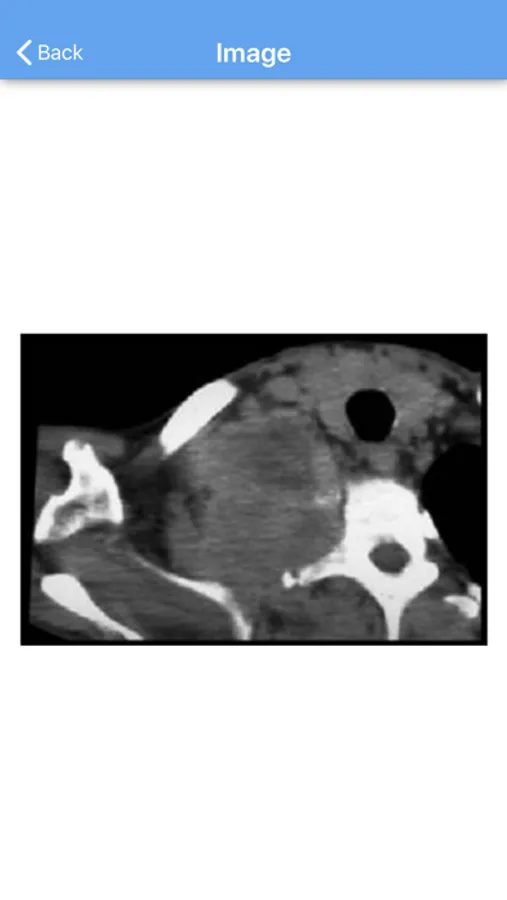

Self Education Self Assessment in Thoracic Surgery (SESATS) is a tool for the training or practicing Thoracic Surgeon to demonstrate his or her cognitive skills for the field. The program covers thoracic surgical disorders of the lung and chest wall, mediastinum, acquired and congenital heart disease, and issues in critical care. The user is presented multiple choice questions for these topics and is given the opportunity to answer those questions. The user is allowed to choose the stringency of the test by opting to be given one or more chances to answer correctly. Some questions have associated images, videos, or CT scans, and all questions have explanatory critiques and literature references which can be viewed after answering the question.